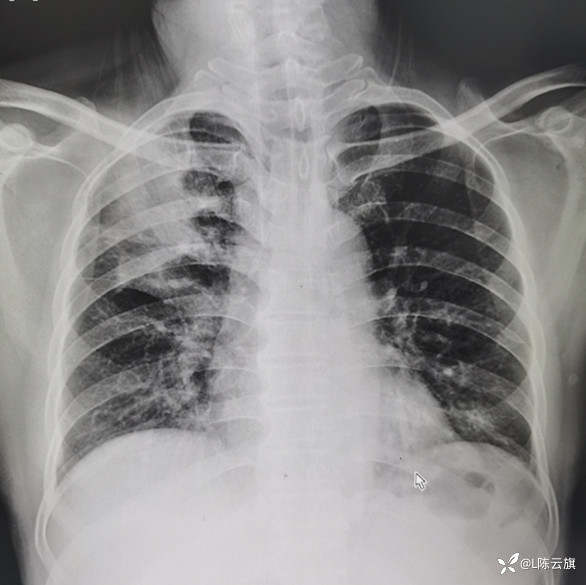

[2404胸部影像病例] 正侧位胸片所见 分别是什么基本病变?如何诊断?

1、患者男,现在59岁,胸部正位片(一)是患者6年前以精神病收住院患者所照的胸片,当时的病史已不详;胸部正侧位片(二三)是现在新入院的照片,没有明确的呼吸道症状和病史!期间是否有过照片已查不到,但患者家属说未作过真正的系统治疗!

3、结合CT所见结论是:①.6年前胸片(一)所见是 渗出性病变--平片表现 右上中肺野大片状密度不均阴影,两下肺野小量小斑点片状影;②.现在的胸片(二三)所见是 右上肺野较多量粗条索状密影,大部分边缘清楚,左下肺野小片阴影已消失,右下肺纹理明显增粗增强;③.CT片证实右上肺病变为纤维性病变,但仍有小部分边缘欠清;④.最后诊断为:右上肺结核大部分纤维硬结。

胸片(一)